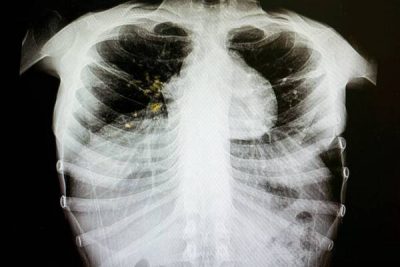

Министр здравоохранения Украины Максим Степанов заявил, что последствием так называемой оптимизации в сфере медицины, которая предусмотрена вторым этапом реформы, может стать вспышка туберкулеза в стране.

«Это не оптимизация, а банальное сокращение. Последствия будут такие, если мы сейчас не остановим этот процесс: как минимум, мы получим через 2-3 года рост заболеваемости на туберкулез на 30%. Увеличится и процент смертей из-за сокращения медработников, речь идет о тысячах медиков», – заявил Степанов.

Он подчеркнул, что не готов мириться с этим, и пообещал уже в ближайшие дни найти решение, как будут финансироваться противотуберкулезные диспансеры. Сейчас же, по словам министра, ситуация критическая – многим учреждениям не хватает до 80% необходимых денежных средств.